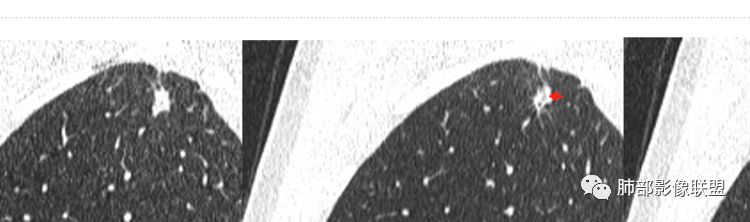

细支气管畸形肉芽肿:即支气管畸形结节,指的是终末段的支气管,细支气管及以下;影像特征,有2-4个眼睛一样的扩张细支气管,如金鱼眼睛,外侧壁已经在结节外(没有异常肺组织);这些扩张细支气管缺乏张力,一般没有被撑圆。一般考虑为先有细支气管畸形,然后才有炎症和纤维组织增生。结节可以是实性,边缘平整锐利,凹陷,不如早期腺癌的饱满,若结节周围有磨玻璃区经常边界不清楚。

三角形轮廓——三角形边缘,尤其是锐三角形病灶是最不支持恶性肿瘤的。

棘状突起——小病灶边界清楚,棘状突起或长条索影,如果是炎性,时间够漫长。

相邻胸膜增厚——周围肺组织小结节影,肺尖胸膜结节样增厚,范围较广,支持慢性病灶。

1.胸膜下不规则结节影,相对单发和或局限,略散,呈三角形,星芒状长条索,周围细小结节,胸膜增厚黏连。继发性肺结核可能性是最大的!尤其是缺乏其他(如肺炎)相关病史。